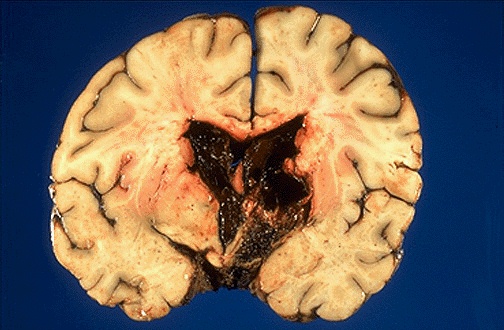

| The intraventricular and intracerebral hemorrhage seen here resulted from a ruptured vascular malformation. The hemorrhage from such a lesion (which is most often histologically an arteriovenous malformation--AVM) can be intracerebral or extend into ventricles or subarachnoid space. |